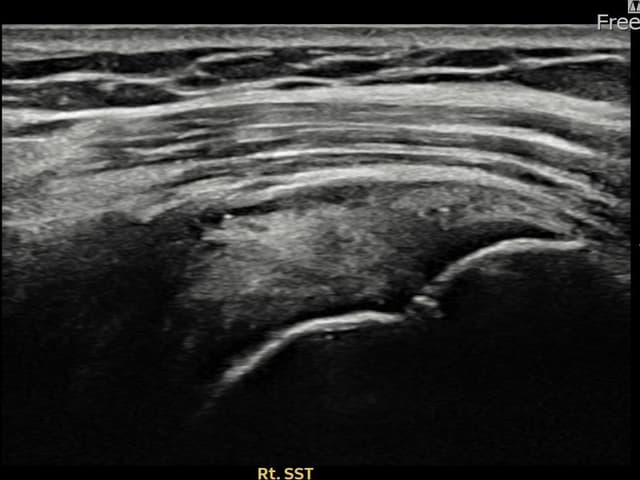

実際の患者様の施術前後の超音波画像。

手術なしで実現できる回復をご確認ください。

[経過期間: 23.10.05~23.12.07]

[縫縮術] 超音波検査にて右 棘上筋腱 付着部部分断裂(10mm × 4mm (腱厚の約42%欠損))を確認。縫縮術施行後、腱の連続性が回復し、日常生活に復帰されました。